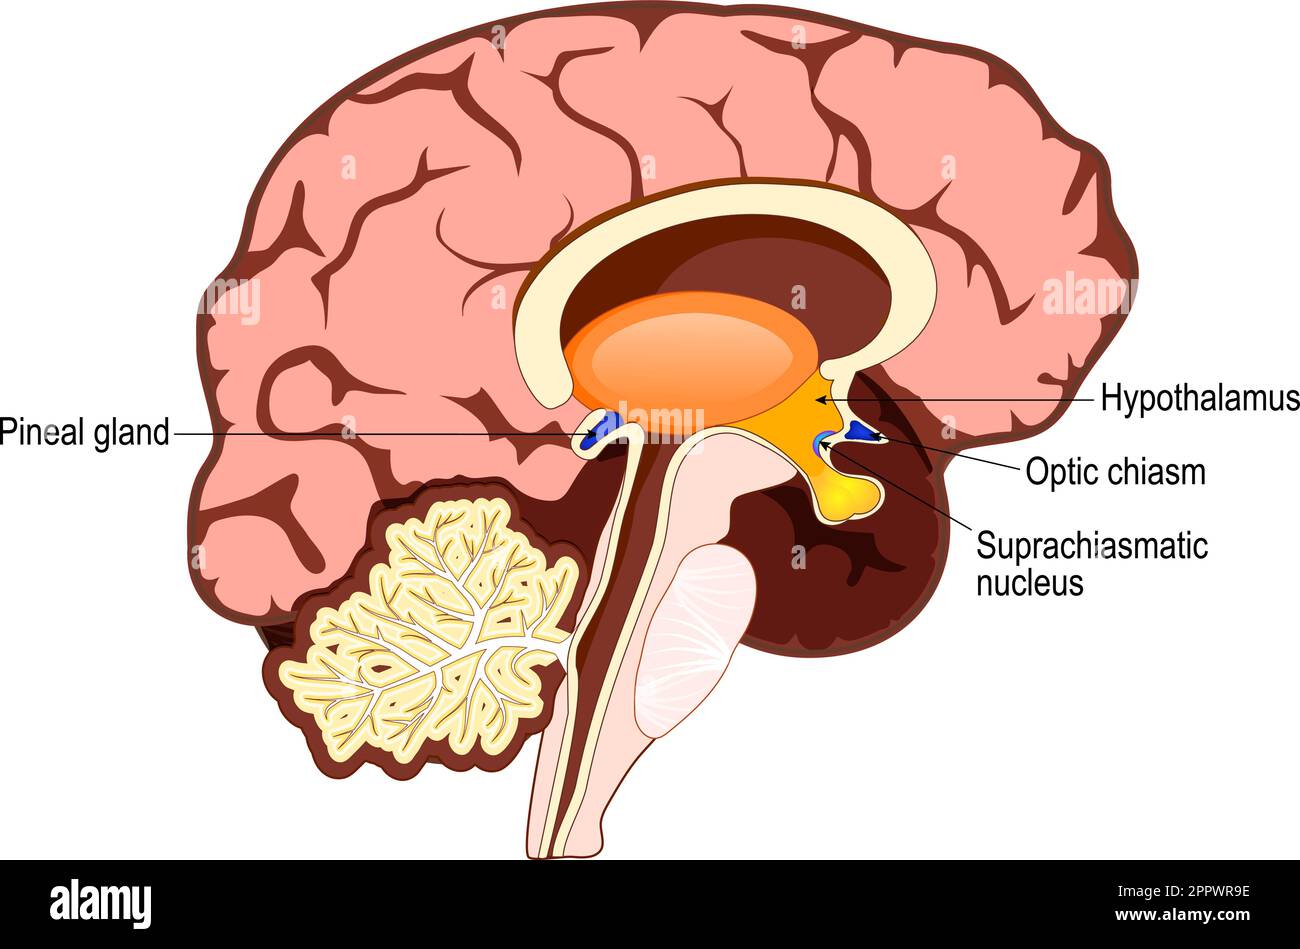

RF2PPWR9E–Cervello umano con parte del sistema limbico e corteccia cerebrale, nucleo suprachiasmatico, chiasmo ottico, Ipotalamo, E Pineal Gland